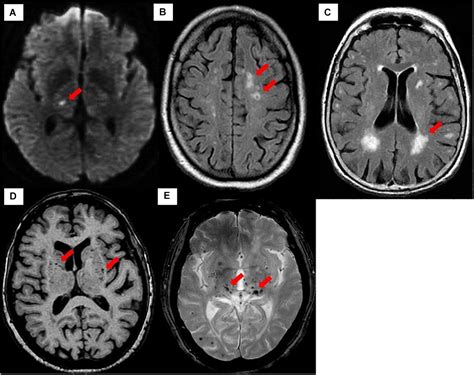

• Imaging Tests: Such as ultrasound, CT scans, and MRI to visualize the blood vessels and assess blood flow.